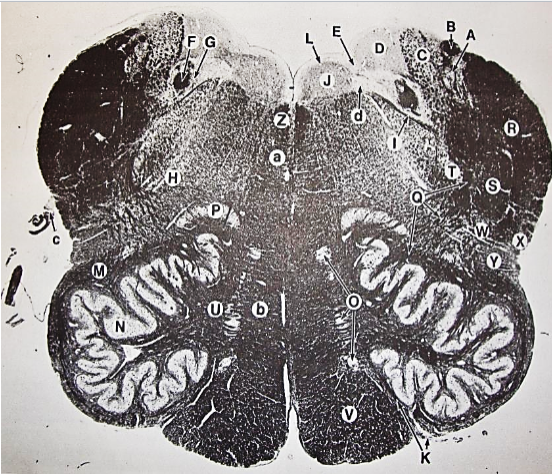

A

Fasciculus gracilis

B

gracile nucleus

C

fasciculus cuneatus

D

cuneate nucleus

E

spinal trigeminal tract

F+G collectively

spinal trigeminal nucleus

H

accessory nucleus

I

pyramidal decussation

J

rubrospinal tract

K

posterior spinocerebellar tract

L

anterior spinocerebellar tract

M

lateral spinothalamic tract

N

anterior spinothalamic tract

O

lateral vestibulospinal tract

P

medial longitudinal fasciculus

Q

tectospinal tract